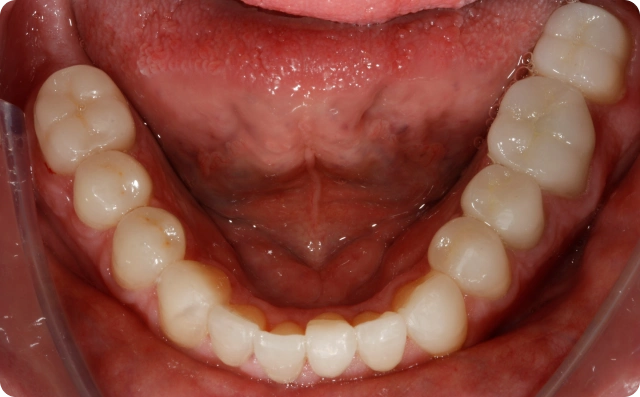

Depois

Foram confeccionadas facetas cerâmicas de dentes caninos a caninos superiores e inferiores, ponte fixa na região superior direita e coroas unitárias em dissilicato de lítio nos pré molares e molares.